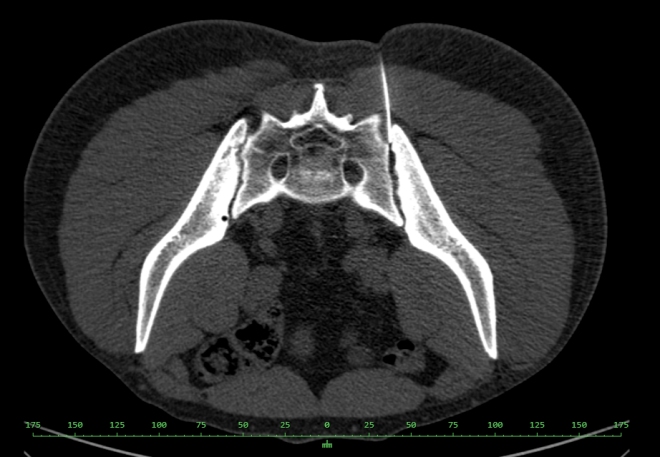

Po punkci kloubu pod CT kontrolou (obr.3) s podáním KL (Optiray 350) bylo podáno RF, následně aplikován 0,1 ml Depo-Medrol s 0,2 ml 1% Mesocainem.

/ Obr.3.: Aplikace RF pod CT kontrolou - zavedení jehly do levého SI skloubení.